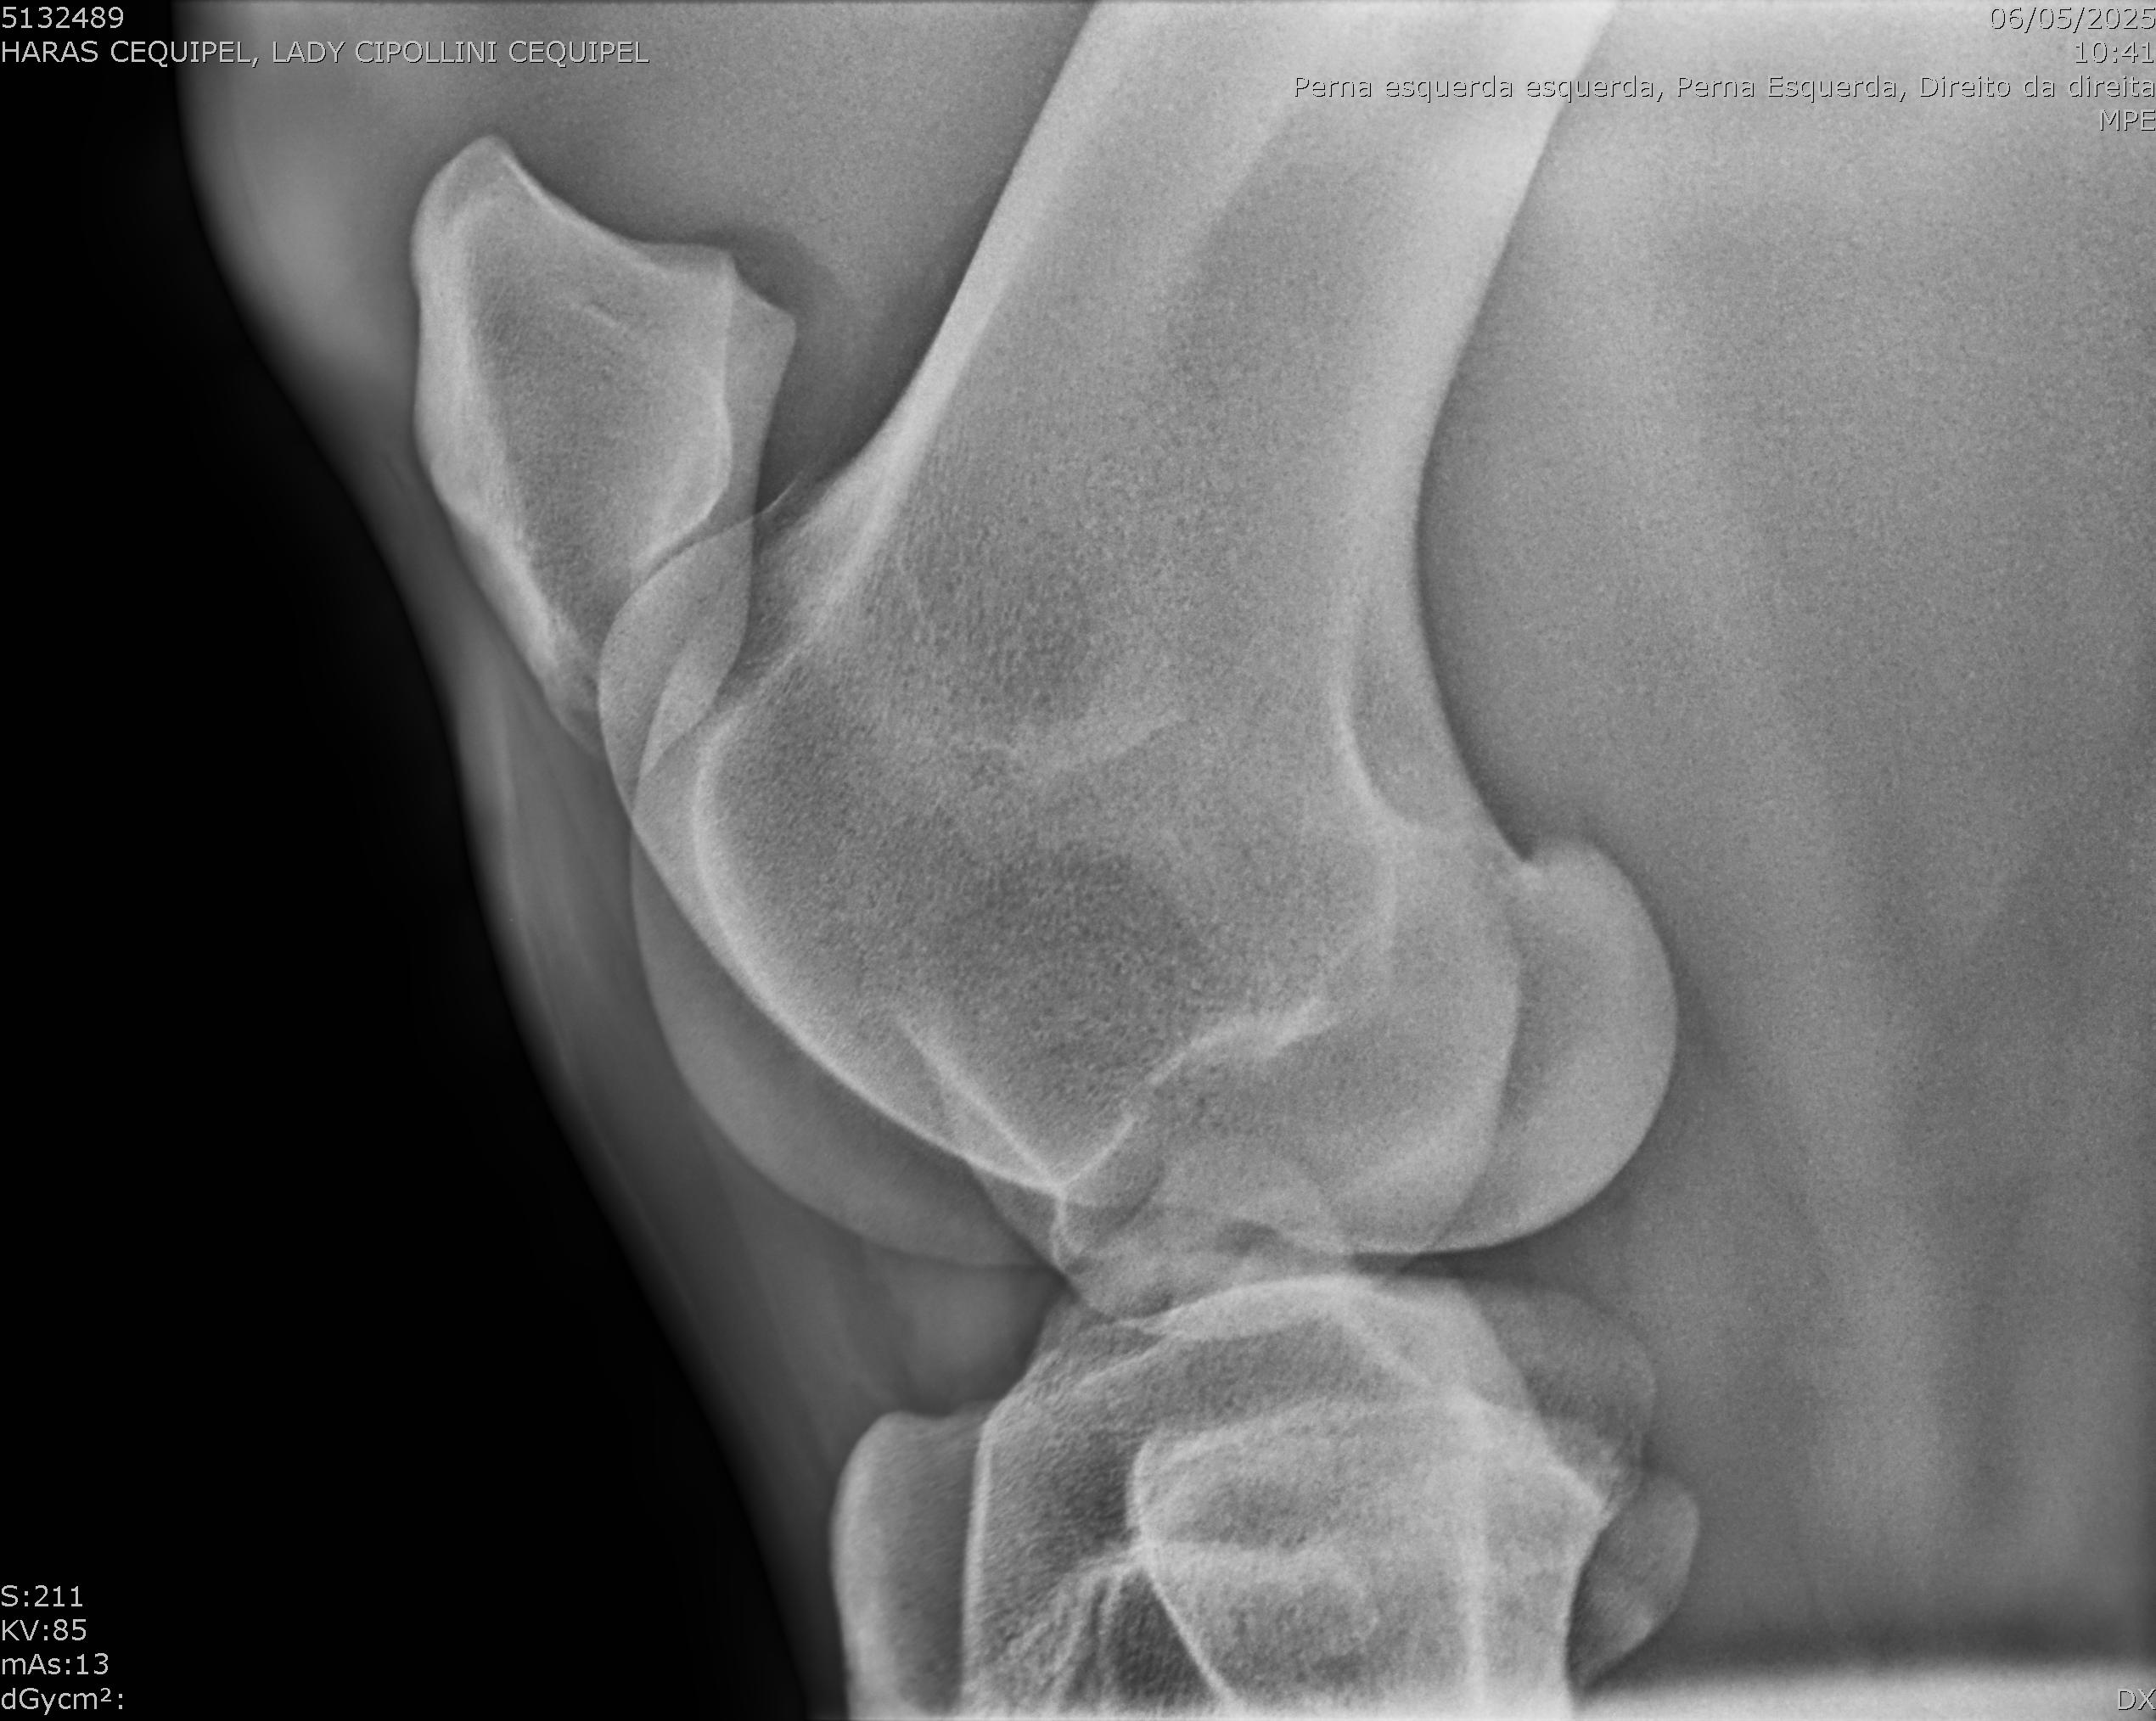

:: RAIOS-X DO LOTE